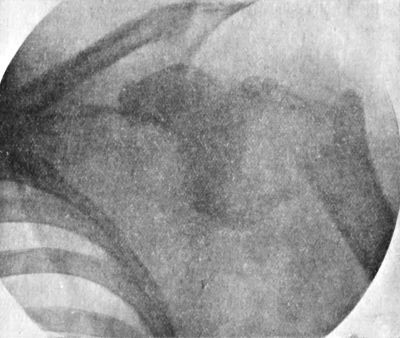

203 104.Radiogram of Specimen of Arthropathy of Shoulder in Syringomyelia

204 105.Radiogram showing Multiple partially Ossified Cartilaginous Loose Bodies in Shoulder-joint